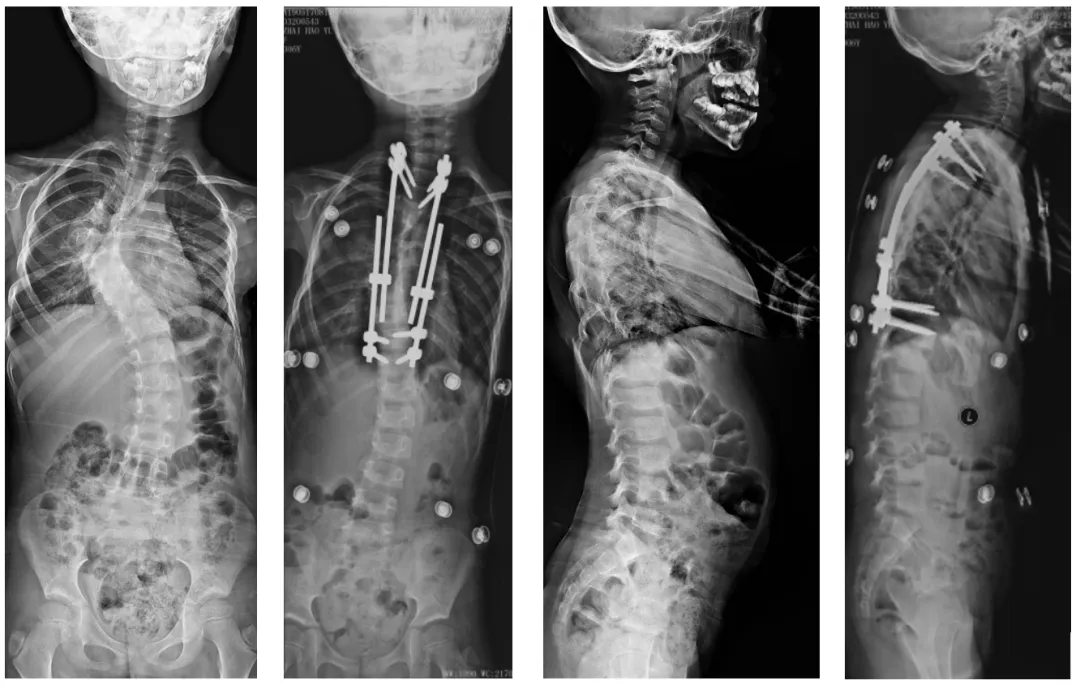

Preoperative → growth rod implantation → full-length piece orthotopic after 6 adjustments

2024-01-30: aggravation of scoliosis deformity

(5) In-situ locking screws, C-arm fluoroscopy shows satisfactory position of the nail-rod system.

Postoperative images